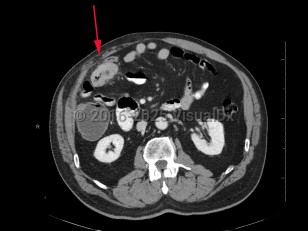

Colon cancer

Colorectal cancer is the second leading cause of cancer death in the United States. Advanced age, male sex, smoking, a family history of colorectal cancer, and inflammatory bowel disease (especially ulcerative colitis) are the strongest risk factors for developing colorectal cancer. Overall, the incidence of colorectal cancer in older patients, particularly those aged 65 years and older, is declining, likely due to a combination of screening and changes in risk factors (eg, decreased smoking). But for patients aged younger than 55 years, the incidence of colorectal cancer has been rising. In younger patients, hereditary factors such as polyposis coli, MUTYH-associated polyposis, and hereditary nonpolyposis colon cancer (HNPCC) also increase the risk of colon cancer development. In many instances, this risk can be modified by screening or surveillance colonoscopy, as most colorectal cancers arise from adenomatous polyps, which can be fully resected. Lynch syndrome is associated with 3% of all new cases of colorectal cancer.

The most common sites of metastasis of colorectal adenocarcinoma are the liver and lungs; rarely, metastatic oral lesions occur. Cutaneous metastases of colon adenocarcinoma most commonly occur on the abdominal skin and may occur in the area of abdominal surgical scars.

Prognosis is related to cancer staging (tumor depth, lymph node involvement, metastatic spread) at time of diagnosis. Treatment often includes a combination of surgical resection and chemotherapy.